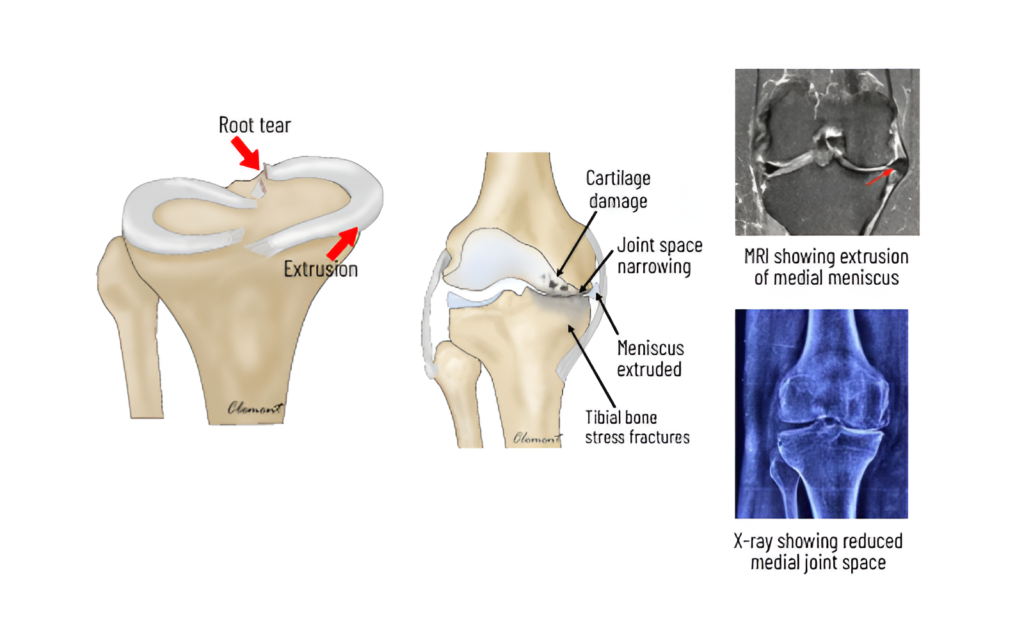

Meniscus roott ears

Root tear refers to detachment of meniscus from its bony attachment. It is a devastating injury as the meniscus is pushed out of the joint and shock absorption is completely lost . This results in overloading of the inner compartment leading to accelerated wear and tear ( arthritis)

Root repair is done using a keyhole procedure called arthroscopy. Two to three strong sutures are placed in the torn end and brought out through a tunnel in the bone. The sutures are fixed onto the tibia bone using titanium buttons. This root repair restores the protective function of the meniscus. Symptoms History of a minor twisting injury or strain with a popping sensation, followed by pain on the inner side of the knee—worsening at night while lying down, when the knees touch each other, and during turning positions in bed—may lead to bow-leg deformity and limping in the later stages.